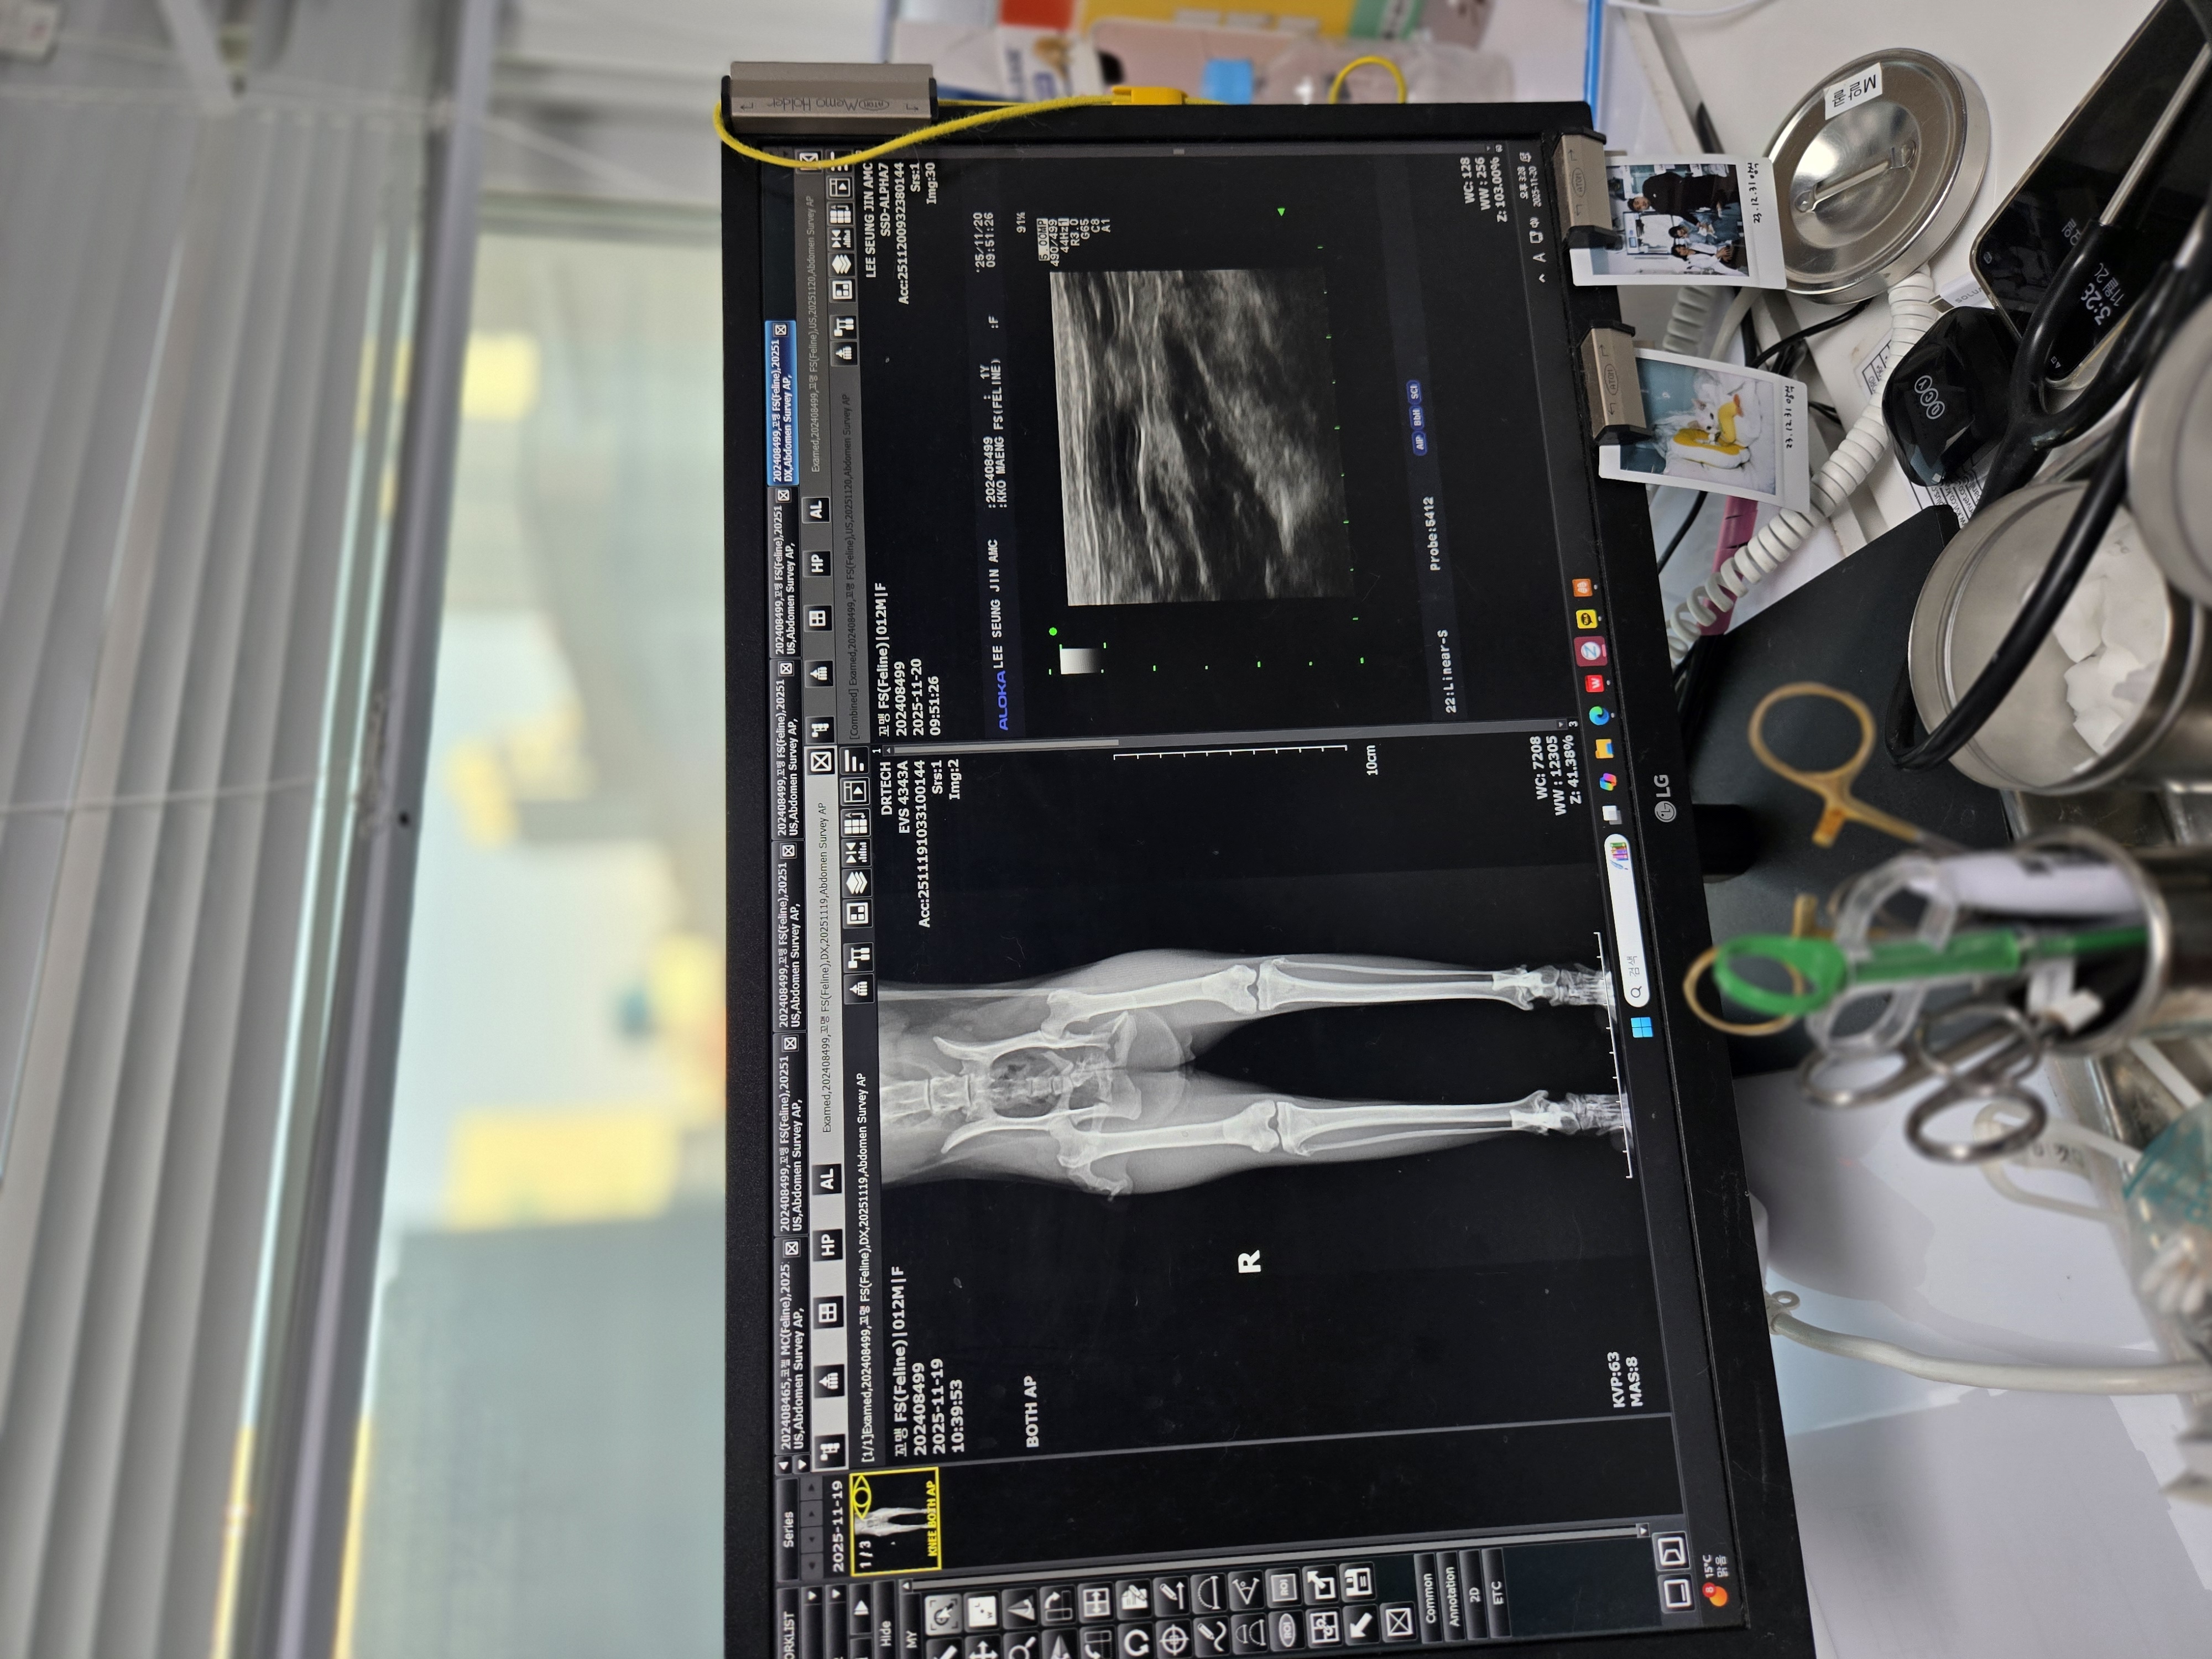

| 대상묘 병명 | (교통사고) 골반 골절 좌측 신장 신 우 확장 위 요 관 일부 확장 |

| 치료과정 | 아는 지인의 소개로 길냥이 할인 해주는 병원 갔는데 저의 예상 과는 다르게 교통사고 골반 골절이고 내부 장기 출혈 우려가 있아ㅓ서 ct나mri되는 2차로 가라는 거였어요 내부 출혈만 없음 수술은 안해도 된다 보행에 지장이 없기 때문에... 수술은 신경이 많이 지나 가는 자리라 어려운 수술 이니까 2차 병원 잘하는데 가서 하라고 그리고 오늘 소변이나 대변서 피가 섞여 나오면 무조건 응급이니까 2차 가야한다 이렇게 듣고 병원 나오는데 신랑이랑 저랑 멘붕이 왔어요 2차는 생각도 안하고 있었는데 어떡하지 병원 소개해주신분도 같이간 언니도 다들 한숨... 2차는 너무 비싼데 했네요그러던 도중에 꼬맹이 소변에 살짝 혈흔이나와서 어디로 가나 했는데 언니가 이승진도 ct mri 다 있다고 울산서 잘 한다는 병원 인데 한번 가보자 그리고 어디 지원 받을 수 없나 알아보던 중 고보협이 생각나서 급하게 지원 신청하게 되었어요 한번도 지원 받은 적 없고 좀 까다롭게 되어 있어서 한번도 안했눈데 이번에 신청했어요 원장님께 앞전 진료 말씀드리니 엑스레이 초음파 먼저 보고 꼭 필요하면 ct나mri찍자고 하시네요 엑스레이 초음파 혈액검사 한 후 제 예상과 달리 교통사고는 수술 안해도 된다 하시고 다른병이 발견 되었어요 좌측 신장 신우 확장 요관 일부 확장 원장님이 그림 그리면서 설명해 주시는데 신장밑 관하고 연결된부위 거기 윗 부분 부분확장 신장 밑 천공 일단 수액 항생제 3일 치료후 먹는약으로 5일 먹고 재검헤보고 결과보고 이야기 자고 하셨어요 질염도 있다고 입원시키고 저녁에 메시지 왔는데 뇨검사상 혈액 염증세포 검출 된다고 직접적인 세균은 확인되지 않지만 가능성 있다고 신우신염에 준하여 치료한다 이렇게 왔어요 입원 시키고 3일동안 면회갔는데 거의 움직임이 없고 살도 좀 빠진 상태 매일 사진과 컨디션이 어떤지 카톡으로 오는데 사람 보이면 숨고 움직임이 없다 퇴원 잘하고 집에 와서도 똑같아요 숨어서 아예 안 나오고 하기야 뼈가 골절 되었는데 얼마나 아프겠어요? 26일은 항생제 캡슣 츄르에 묻혀서 항상 먹어 왔는데 그날 따라 입안에 걸렸는가 씹다가 거품 물고 난리가 나서 병원에 전화했더니 대게 쓴 약이라네요 담날은 아예 약을 귀신같이 골라내서 병원 다시 가서 물약으로 된 항생제도 받아왔어요 29일 재검일이라 다시 다녀 왔는데 신우 확장이랑 요관 확장은 낫지 않을꺼 같다네요 원인도 모르겠다 하시고 추측으로는 선천적 기형이거나 tnr했을때 잘못 되었을 가능성 교통 사고로는 이렇게 될 수 없다 충격 받았을 때 위치가 아래쪽 방광 이나 요도쪽 이어야 된다 그냥 그렇게 추측일 뿐이라고 하셧어요 나빠지지만 않으면 좋을 텐데 만약에 좌측 신장 기능을 잃어도 그래도 하나는 정상 이니까 사는데 크게 지장은 없다 그러시네요 다만 아직 질염도 있고 백혈수 수치도 높으니 2주 항생제 더 먹어보고 다시 검사하자고 하시네요 2주후에 토욜 오후에 예약하고 왔어요 |

| 대상묘 치료중 사진 | ![]() ![]() ![]() ![]() |